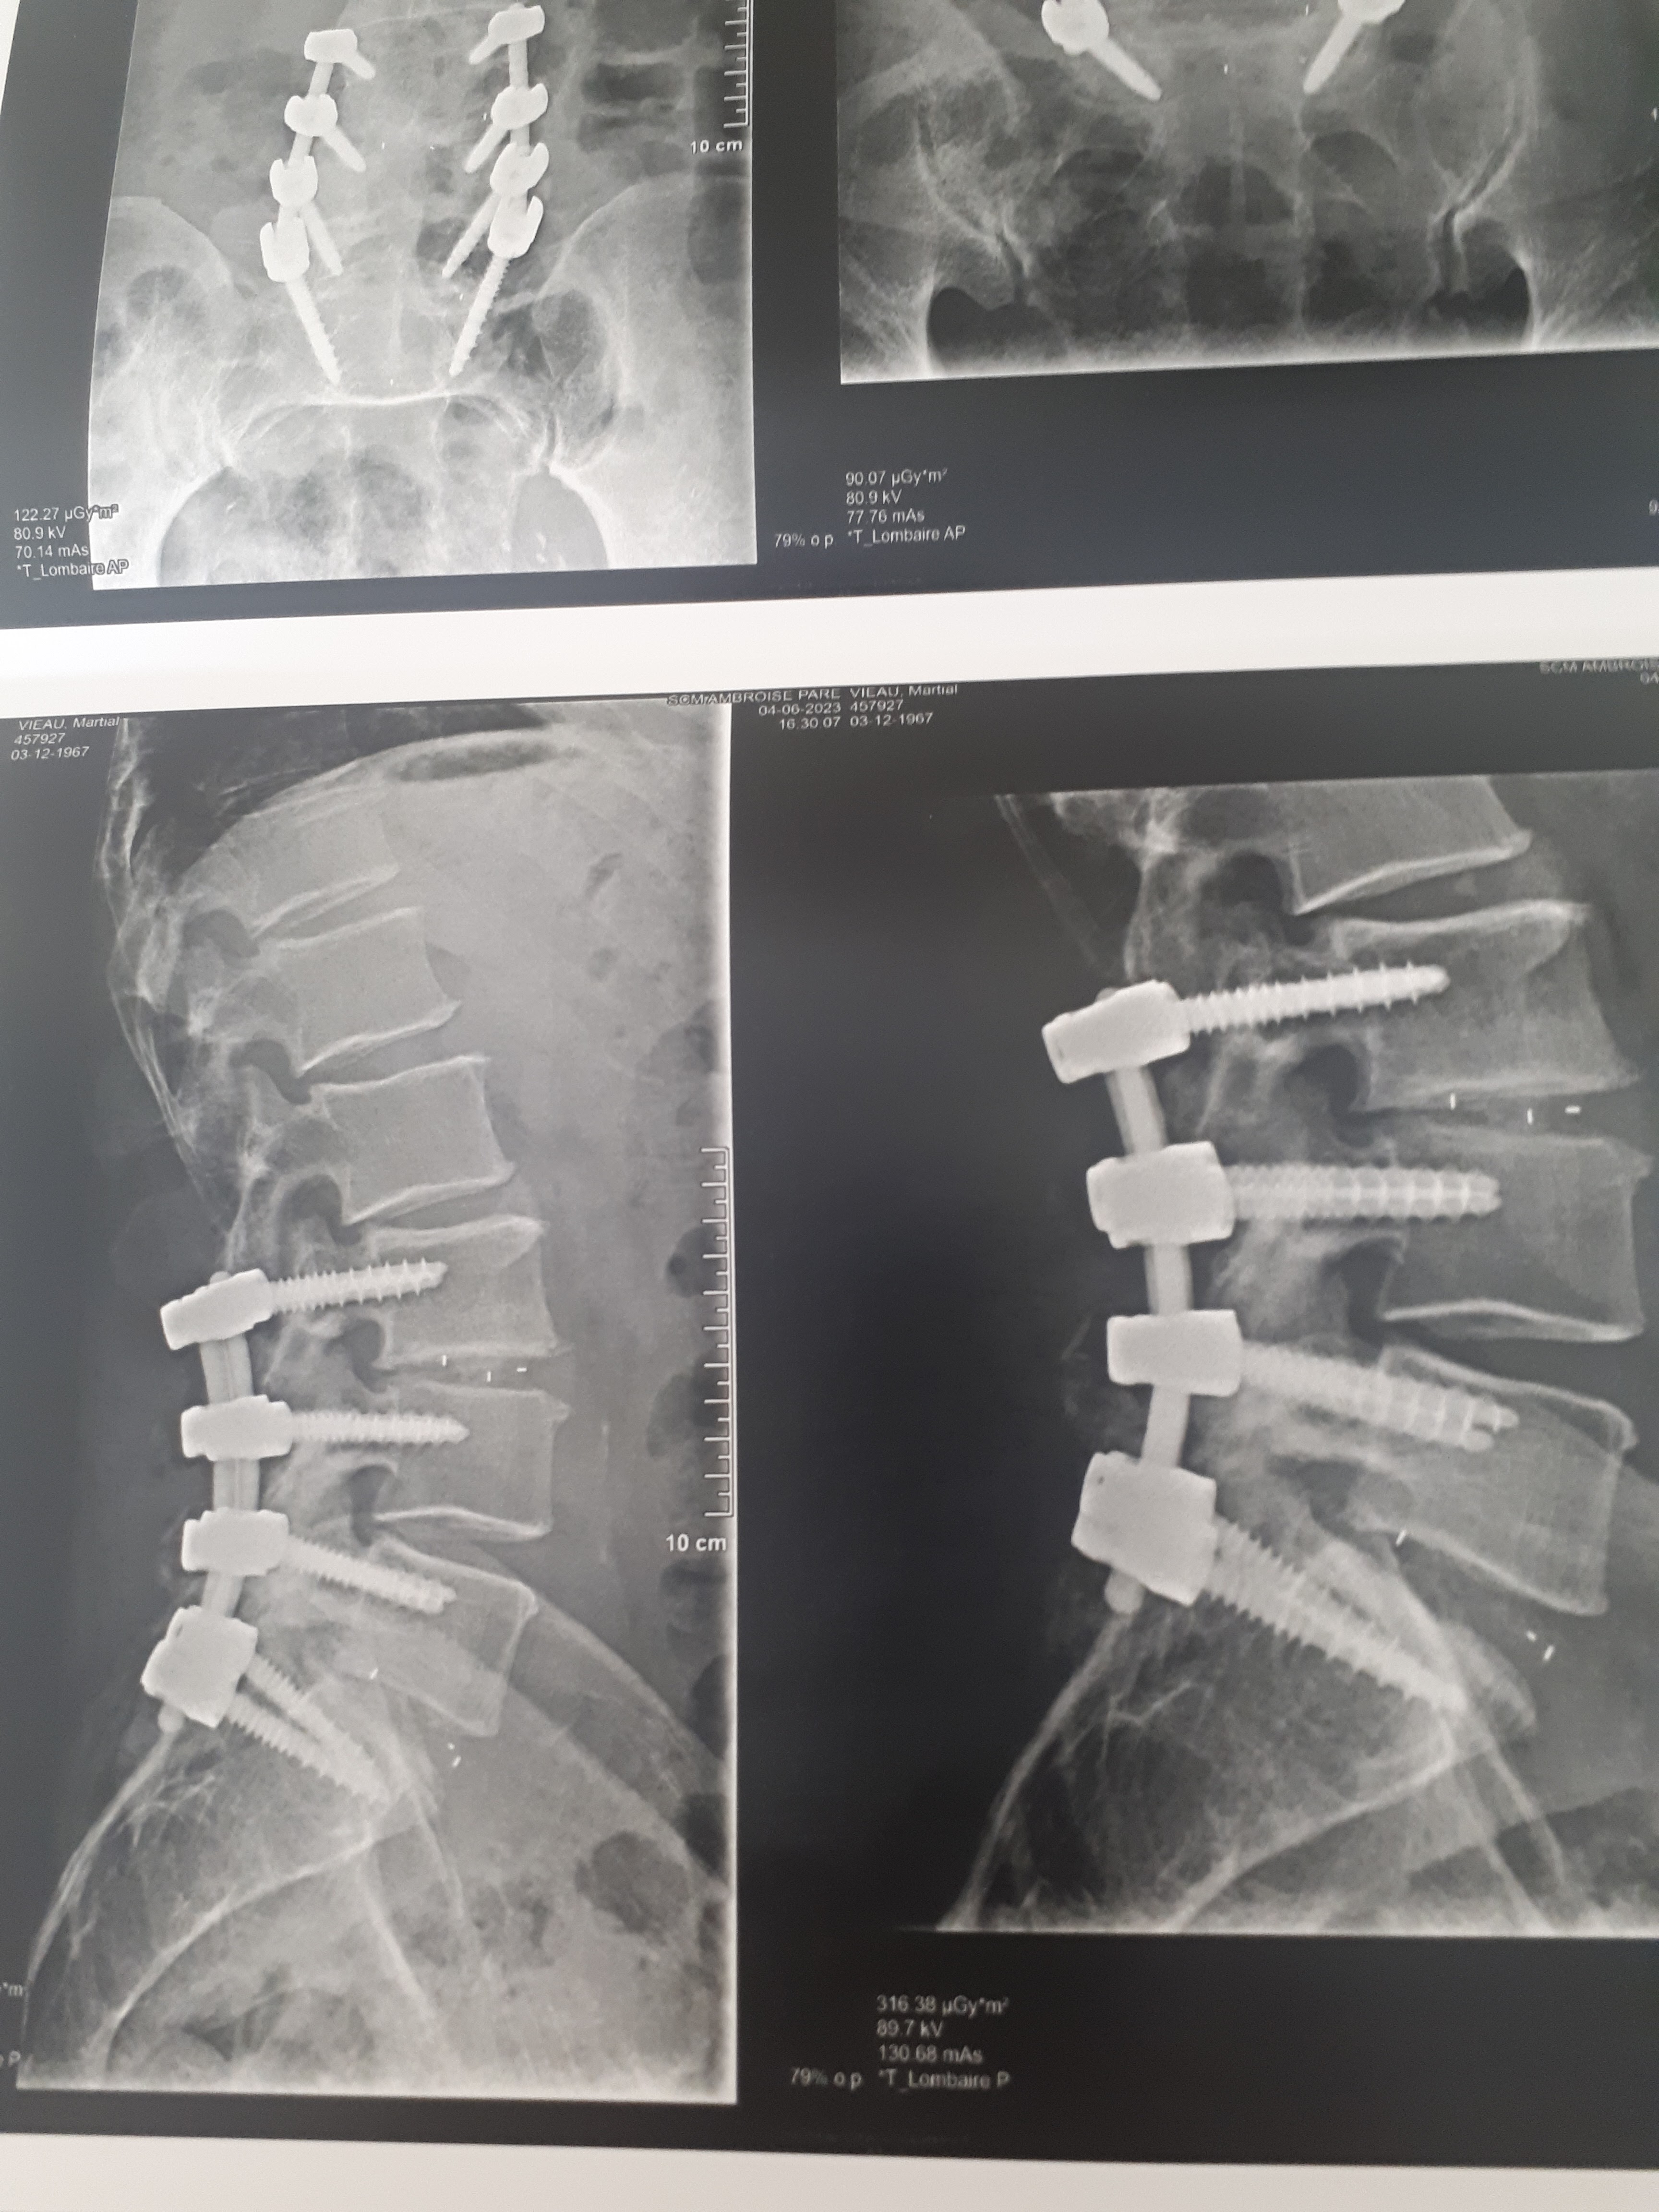

J'ai passé un IRM du rachis complet. La salle d'IRM était utilisée comme entrepôt. Le médecin a pris littéralement UNE MINUTE pour rédiger son rapport dans lequel il déclarait que mon rachis était parfait. En fait, il est soudée à au moins cinq endroits et pleine de déformations, de calcifications et d'érosions. L'orthopédiste a déclaré que j'avais le rachis d'une personne de 90 ans. Lorsque j'ai exprimé ma surprise, le médecin a demandé à voir mes radiographies et a ensuite ajouté une ligne à son rapport en se basant *sur les radios* pour signaler la présence d'une certaine déformation. Il n'a pas précisé quelles vertèbres étaient touchées. Il n'a toujours rien dit sur les autres problèmes, y compris les fusions. Il a conclu que je n'avais pas de maladie du rachis, qui m'empêche d'obtenir une aide médicale. Ce médecin est dangereusement incompétent. Allez ailleurs.